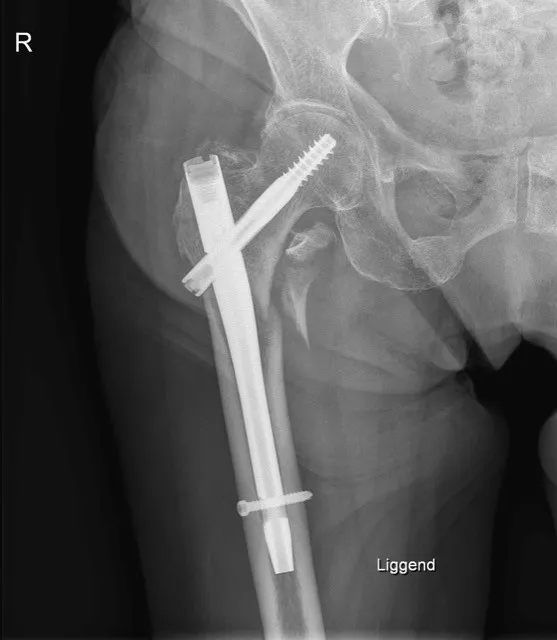

1. Intramedullaire heupnagel (gammanagel)

Bij een pertrochantere of subtrochantere femurfractuur is een intramedullaire nagel vaak de voorkeursbehandeling. Hierbij wordt een stevige metalen pen ingebracht via het bovenste deel van het dijbeen (femur), in het beenmergkanaal. Deze ‘gammanagel’ wordt verankerd met een dwarsschroef in de hals en kop van het dijbeen en 1 of 2 schroeven lager in het bovenbeen. Dit biedt een stevige fixatie voor patiënten die snel weer moeten mobiliseren en geeft minder risico op loslating bij osteoporotisch bot.